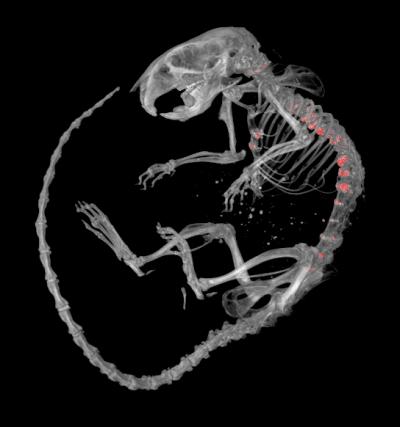

According to The Arthritis Society, the second most common form of arthritis after osteoarthritis is "diffuse idiopathic skeletal hyperostosis" or DISH. It affects between six and 12 percent of North Americans, usually people older than 50. DISH is classified as a form of degenerative arthritis and is characterized by the formation of excessive mineral deposits along the sides of the vertebrae in the neck and back. Symptoms of DISH include spine pain and stiffness and in advanced cases, difficulty swallowing and damage to spinal nerves. The cause of DISH is unknown and there are no specific treatments.

Graduate student Derek Bone, working under the supervision of pharmacologist James Hammond, was studying mice that had been genetically modified to lack a specific membrane protein that transports adenosine when he noticed that these mice developed abnormal calcification (mineralization) of spinal structures.

Changes in the backbone of these mice were characterized by an interdisciplinary team which included: Sumeeta Warraich, Diana Quinonez, Hisataka Ii, Maria Drangova, David Holdsworth and Jeff Dixon. Their findings established that spinal mineralization in these mice resembles DISH in humans and point to a role for adenosine in causing abnormal mineralization in DISH.